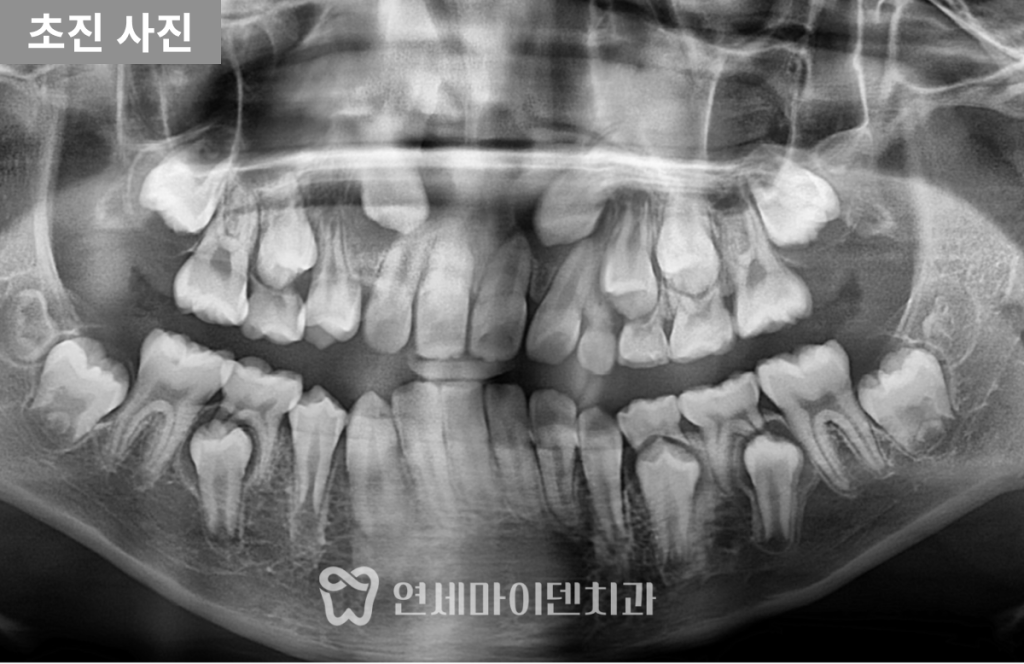

초기진단: 유치 조기 탈락과 송곳니 공간 부족

파노라마 사진을 통해 영구치 송곳니의 위치와 공간 문제를 확인하였습니다.

- 오른쪽 송곳니:

유치가 너무 일찍 빠지면서 공간이 닫혀,

영구치가 올라올 위치가 거의 사라진 상태였습니다. - 왼쪽 송곳니:

유치가 남아 있었지만 송곳니 크기 대비 공간 부족이 확인되었고,

특히 앞니 뿌리 사이로 매복되어 있어

앞니 뿌리 주변의 피질골도 일부 소실된 상황이었습니다.

이대로 송곳니가 자라게 되면

기존 앞니 뿌리를 밀어내어

발치까지 고려해야 하는 상황까지 이어질 수 있었습니다.